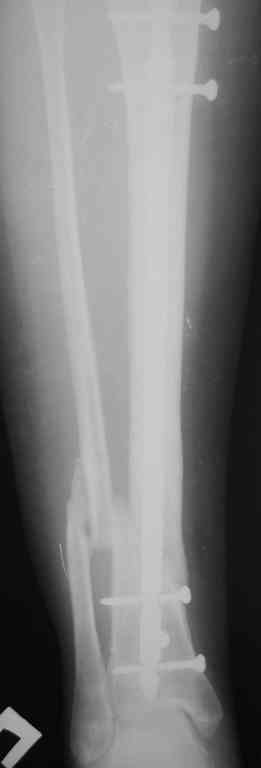

Прилагаются.

Да , обсуждалась и оптимальным штифтом был выбран " Мастер" Остеомед 10 мм и винты 5 мм, но увы все наши благие намерения разбились о нашу действительность и материальные возможности больной, обращение ее в страховую компанию и т.д., вообщем выкручивались из внутренних резервов, а они были такими 9 мм штифт Остеомед, под 4 мм винты. Ограничили нагрузку. Ошиблись еще и с оценкой сращения, дали полную нагрузку+ больная поправилась на 18 кг, и вот теперь имеем , что имеем.

Действитльность и возвожности остались прежнее, во внутренних резервах есть 11 мм стержень универсальный ( реконструктивный) "Деост-CHM" много спиц и аппарат + ось конечности и отломок штифта и надежда на Ваши советы.